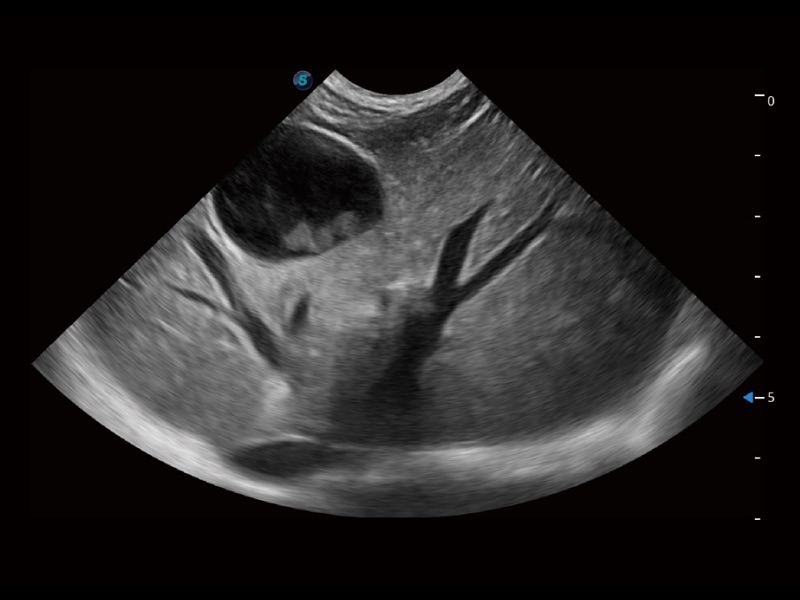

动物是人类最亲密的朋友和最值得信赖的伙伴。亚星官网也一直致力于探索动物专用的超声影像解决方案。全新推出的ProPet系列,是亚星官网在动物超声影像智能化、专业化、精准化的一次跨越式革新。动物不能用言语来表述自己的不适,通过超声影像,ProPet系列搭建了动物医生与不同物种沟通的“桥梁”,为动物医生注入了“治愈之力”。 ProPet 70将是您值得信赖的超声伙伴。它配备了复合材料线阵探头,帮助动物医生获得卓越精准的临床图像。同时ProPet 70直观便捷的操作体验以及专业的测量工具,可为不同体型和生理结构的动物带来全面临床评估,切实为动物医生提供智能、专业、精准的超声影像解决方案。

ProPet 70 进一步提升了微米成像算法,更加注重对基础原始图像的还原和保留,在有效减少斑点噪声、增强组织边界显示的同时,避免过度优化丟失真实的解剖信息。

ProPet 70专为动物医生设计,对不同的动物体型和生理结构作出了针对性的优化。通过动物影像专用软件,可满足个性化的应用需求,帮助动物医生获得更精确的诊断数据。

ProPet 70 全新的动物超声智能软件和丰富的探头群,为动物医生提供了高清晰度和精细分辨率的图像,无论在宠物、马科、畜牧还是实验室动物等应用中都可以轻松应对,为您的日常工作带来满意的体验。